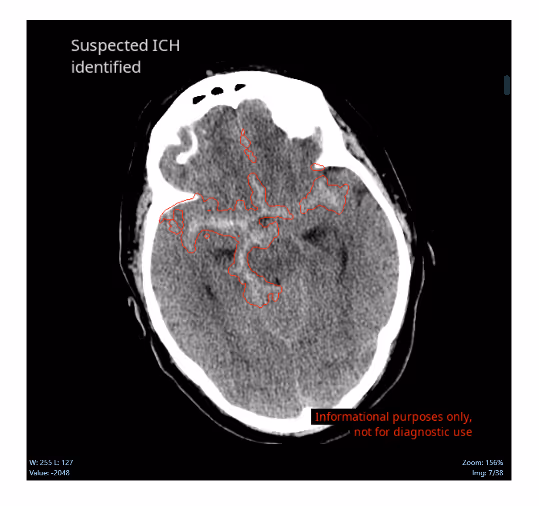

Ferrum Health partners with best-in-class AI providers offering solutions designed to reduce radiology workload and improve patient care.Avicenna Case Study: Acute Subarachnoid HemorrhageHow real-time notification can improve care and efficiency?IntroductionNotification for neuro-critical findings from non-contrast computed tomography (NCCT) imaging of the head can range upwards of 4 hours even in emergency room and critical care settings, which can delay and degrade patient management.Clinical CaseA 61-year-old man presented with altered mental status after being found face down following a fall. Upon presentation, he was alert but remained confused. An NCCT of the head was ordered.

Following imaging acquisition, the case was not reviewed until two hours later, which revealed an acute subarachnoid hemorrhage, predominantly involving the suprasellar cisterns. A follow-up CT angiography was recommended to exclude aneurysmal rupture.

ConclusionThe mean time-to-notification of CINA-ICH is 22s. Had this tool been deployed, the radiologist would have been alerted at the time of imaging. Moreover, he could have immediately reviewed the case and ordered a CTA while the patient still was in the CT scanner while also alerting neuro-critical care teams. Not only could this have improved patient care, but this would have also saved resources.Note: Segmentation is not currently available for clinical use in the United States. Please see Avicenna outputs documents for more information.Intracranial hemorrhages (ICH) affect over two million people worldwidewith a 40-50% patient mortality rate within one month, and 80% disability despite aggressive care.Quick and accurate early diagnosisof ICH mayfacilitate a prompt therapeutic response, allow fast decision-making, and ultimately improve outcomes.CINA-ICH uses deep learning to identify suspected intracranial hemorrhageand prioritizes those cases in the worklist, dramaticallyreducing turnaround time for head traumaand stroke patients.Interested in deploying CINA-ICH at your health facility? Contact the Ferrum Health team to learn more.